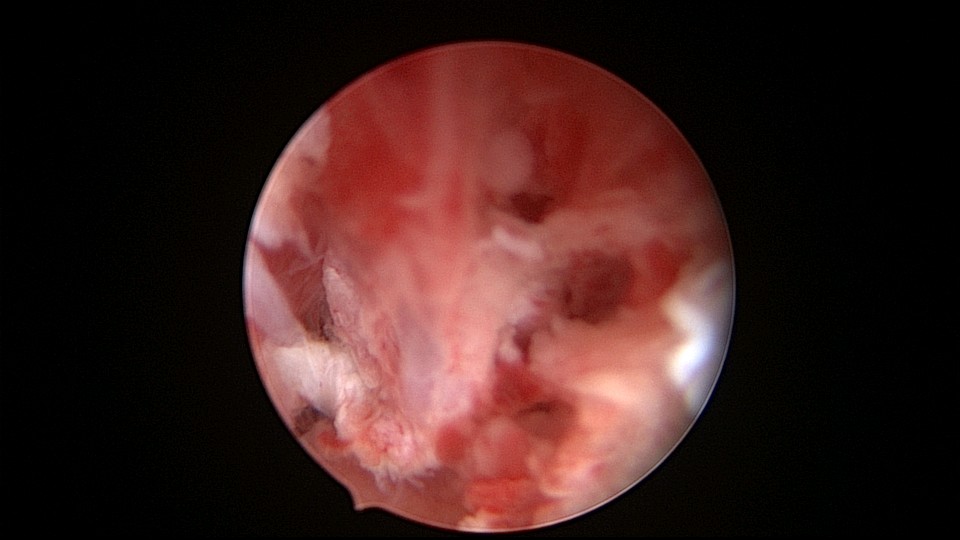

患者48岁,G5P1,剖宫产1次。安环20年,闭经3个月,外院取环失败,形成假道。子宫极度前倾前屈位,宫腔镜见宫颈管上段组织杂乱,左后壁假道,宫腔镜寻找到宫颈内口,艰难进入宫腔,爱母环位置正常,异物钳顺利取出,宫腔无其他异常。